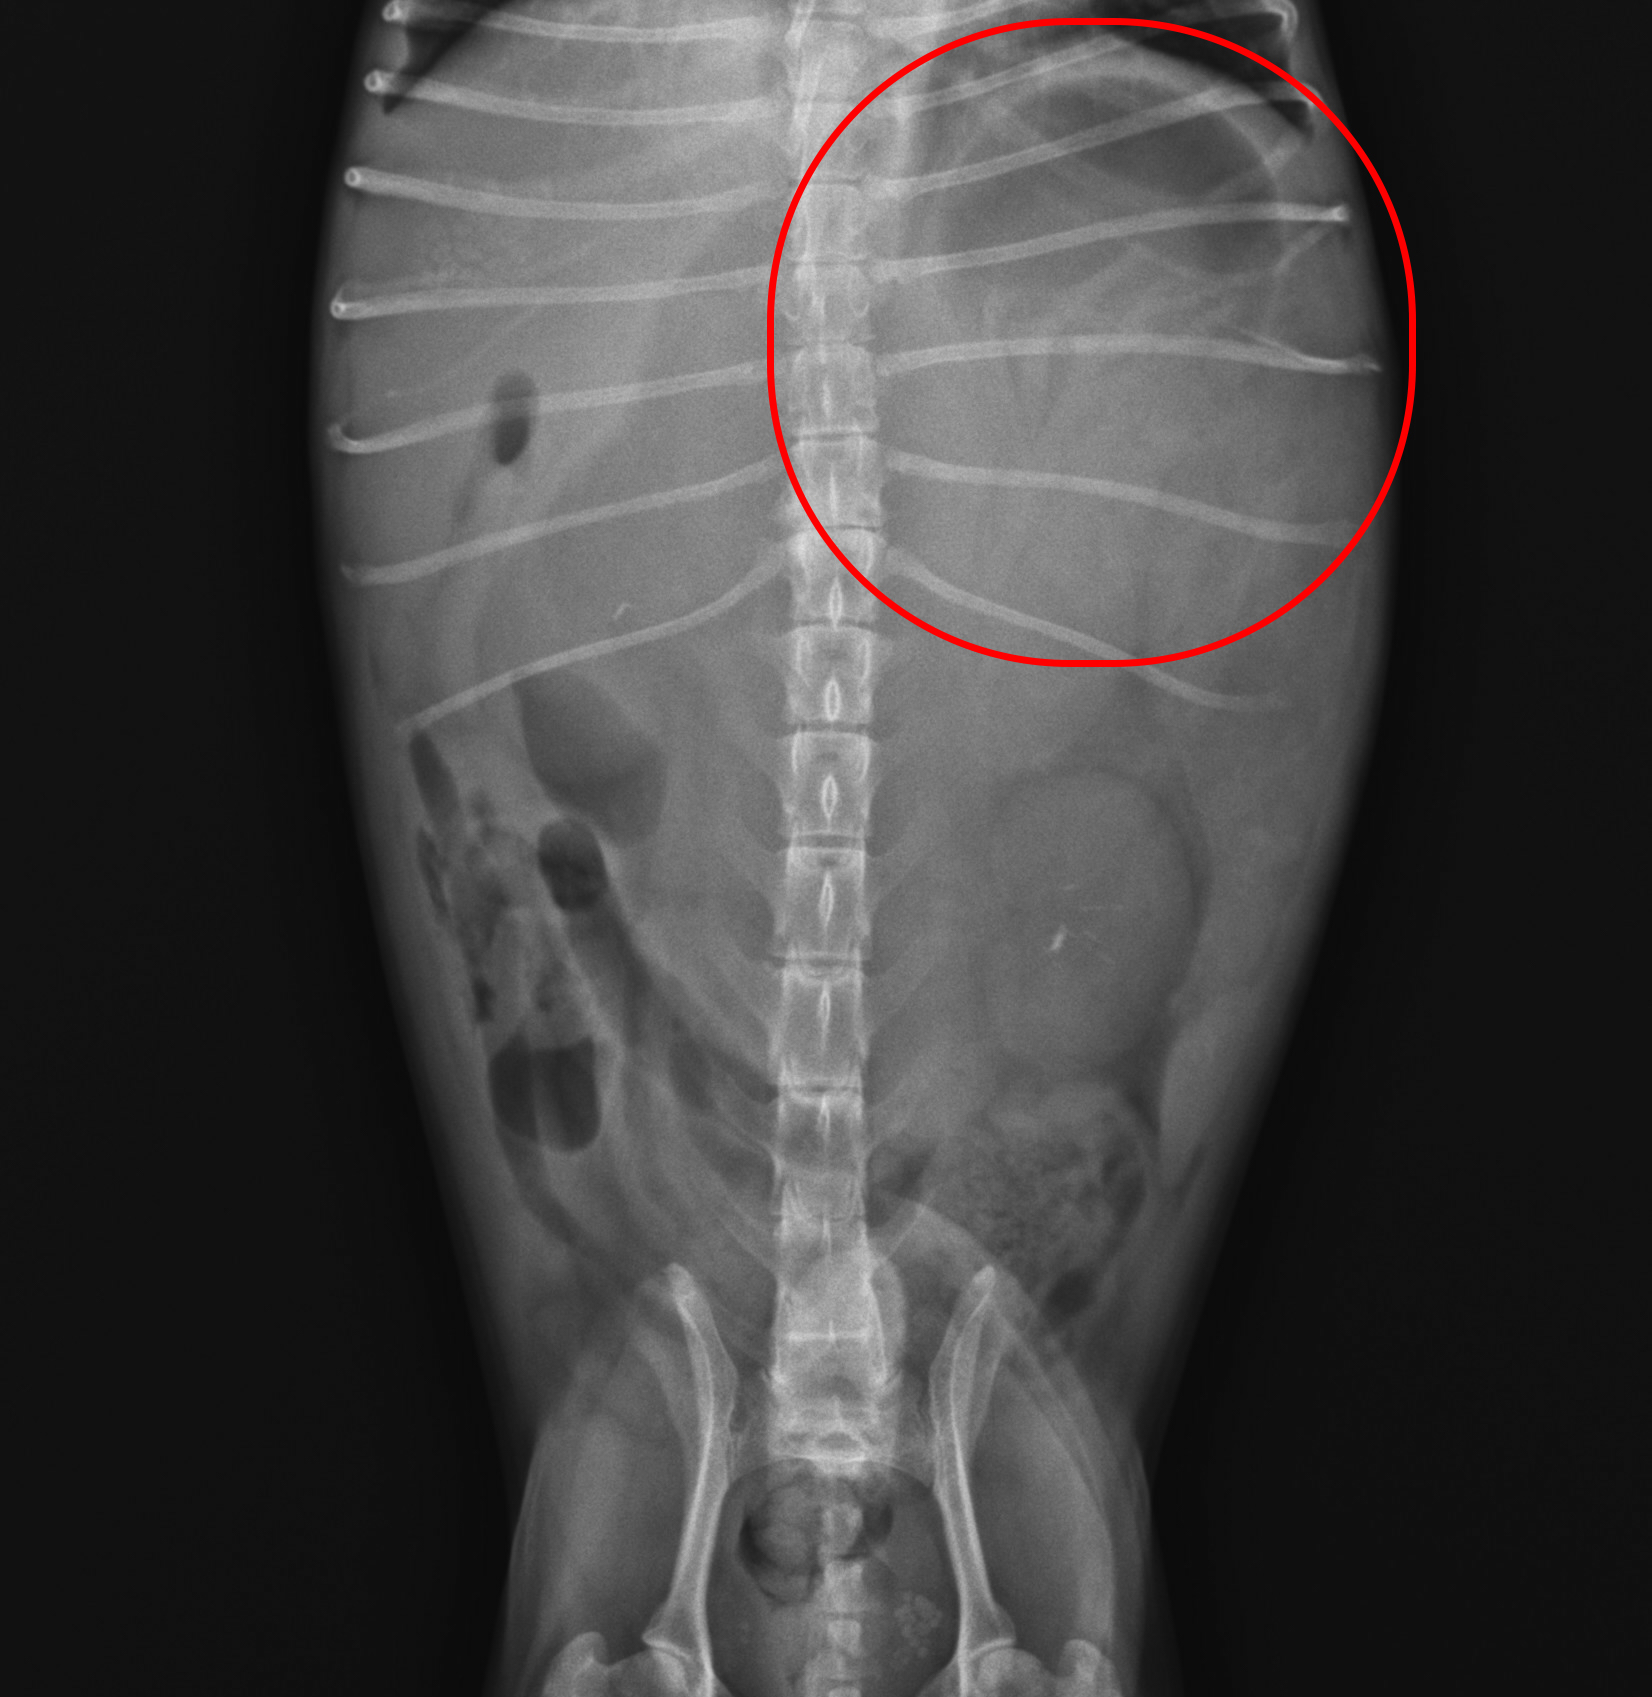

말티즈 아이는 복부전체를 차지할 정도의 큰 종괴가 발견이 되었습니다.

말티즈 아이는 초음파검사에서 기타 장기로의 전이가 확인이 되지않았으나 간유래의 종괴 주변부로 복수가 관찰이 되었으며

CT검사진행을 통해 정확한 전이상태와 종괴평가, 수술가능여부 등의 확인을 위한 검사가 진행되었습니다.

CT검사를 통해 종괴에 대한 정확한 평가가 이루어졌으며 주변장기로의 뚜렷한 전이는 확인이 되지않았습니다 :)